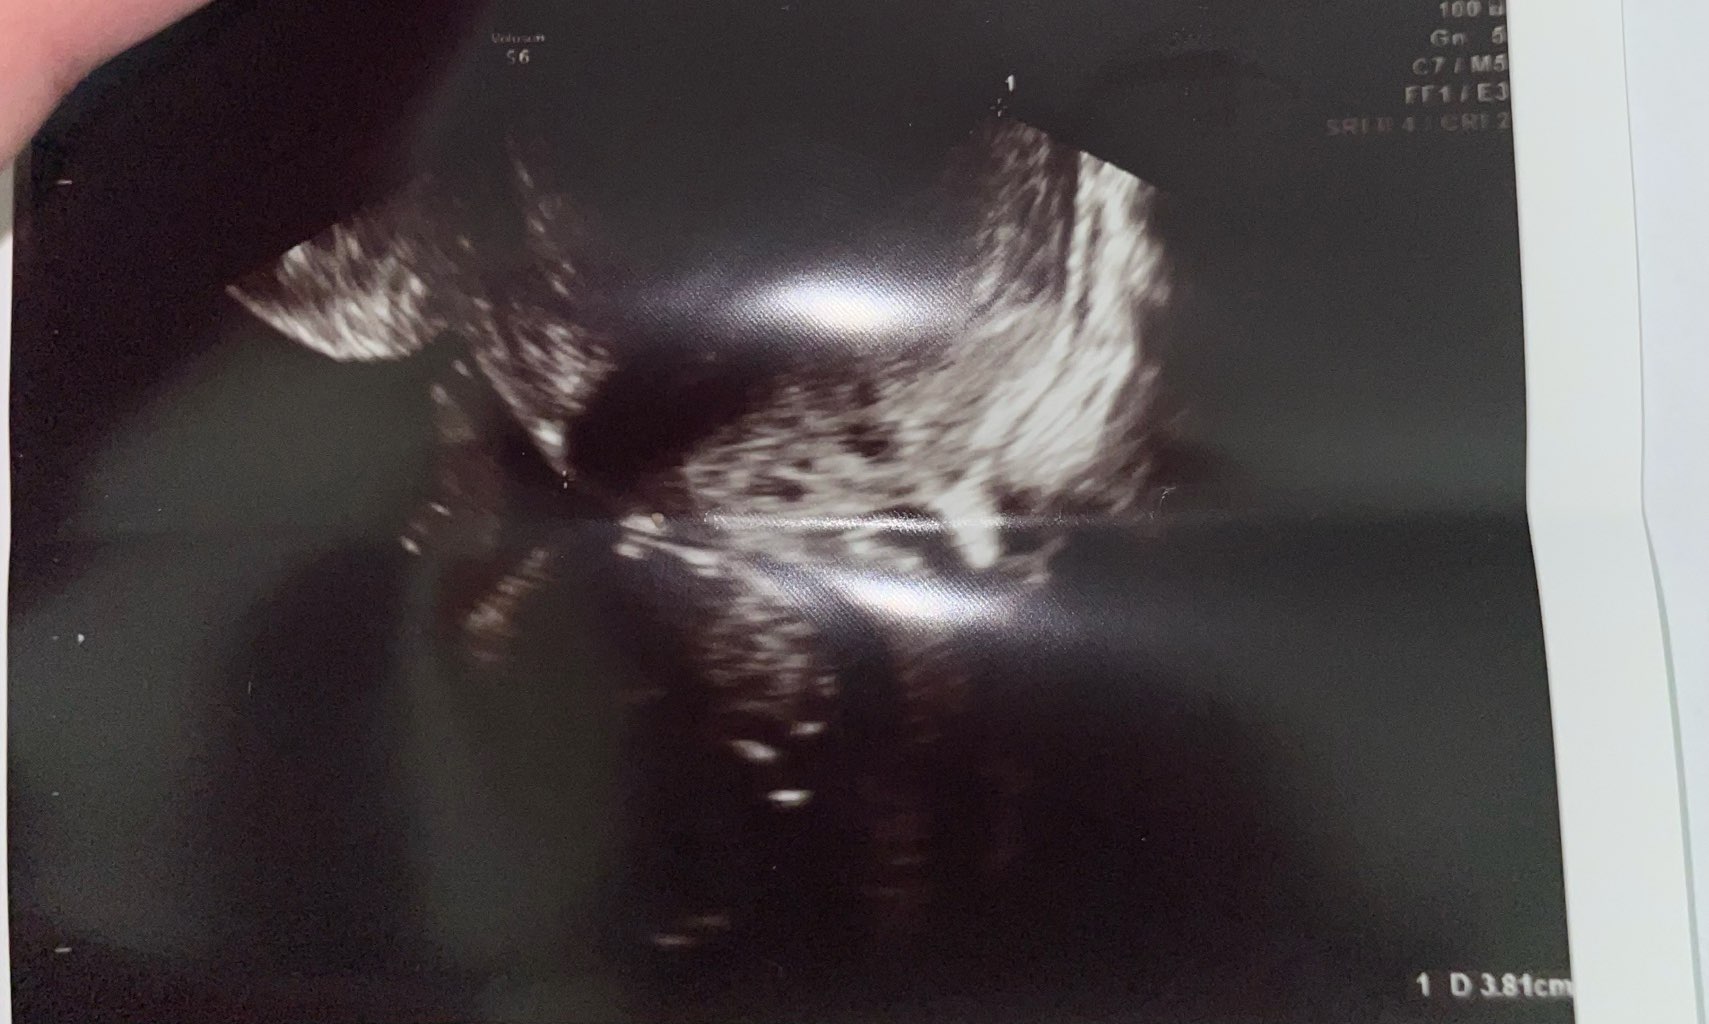

USG

Hej dziewczyny, dzisiaj miałam wizytę kontrolną u swojego lekarza, takie zdjęcie zrobił USG nie wiem czy ja tam nic nie widzę i tak powinno być, czy po prostu nie mogła uchwycić maluszka, jak myślicie 😅